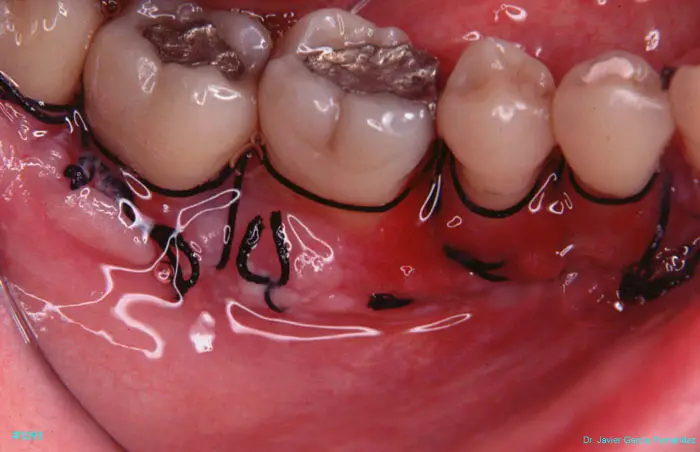

Atlas of Surgical Techniques in Periodontics. Chapter III. Atlas de Técnicas Quirúrgicas en Periodoncia